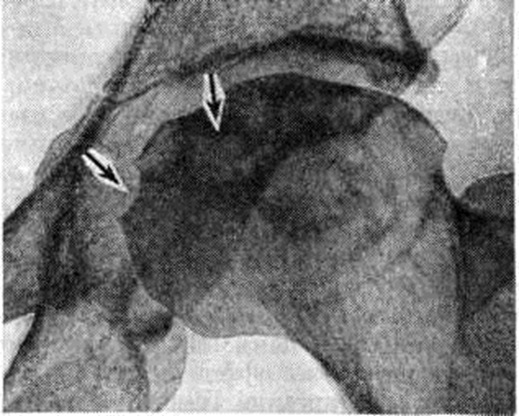

Наиболее часто встречающимся признаком вторичного гиперпаратиреоза при Остеопатия нефрогенная является субпериостальная резорбция (рисунок 1). Она появляется в фалангах и других костях, но фаланги дают более тонкое изображение структуры. Чаще резорбция возникает по радиальной поверхности средних фаланг. Корковый слой костей кажется разволокнённым (рисунок 2). Иногда при Остеопатия нефрогенная можно обнаружить кистозные изменения костей (коричневые опухоли). Субпериостальная резорбция, разволокнение коркового слоя и образование кист, кроме фаланг, наблюдаются в рёбрах, костях таза, ключицах, костях нижней челюсти, бедренных костях, черепе. При Остеопатия нефрогенная своеобразна картина свода черепа, который имеет вид «матового стекла», при более выраженной резорбции изображение костей черепа имеет зернистый вид с более крупными очагами, при этом могут присутствовать участки более плотной кости.